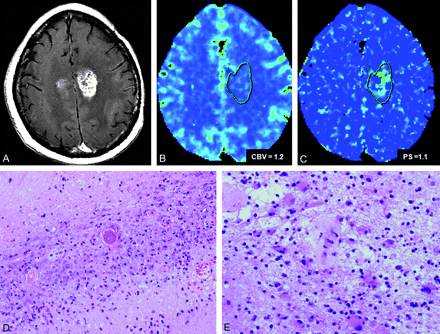

A 41-year-old man with an initial diagnosis of WHO grade II astrocytoma who underwent chemotherapy and RT (IMRT, 63 Gy). A, At 33 months post-RT, follow-up MR image shows development of a recurrent enhancing lesion in bilateral frontal regions. B and C, CBV (B) and PS (C) maps show low rCBV and PS, suggesting TIN. D and E, The patient underwent biopsy. Histopathology slides show pan-necrosis, reactive astrocytosis, necrotizing vasculopathy, and demyelination, with no active tumor foci, suggesting TIN (hematoxylin-eosin, original magnification ×10, D, and ×20, E).